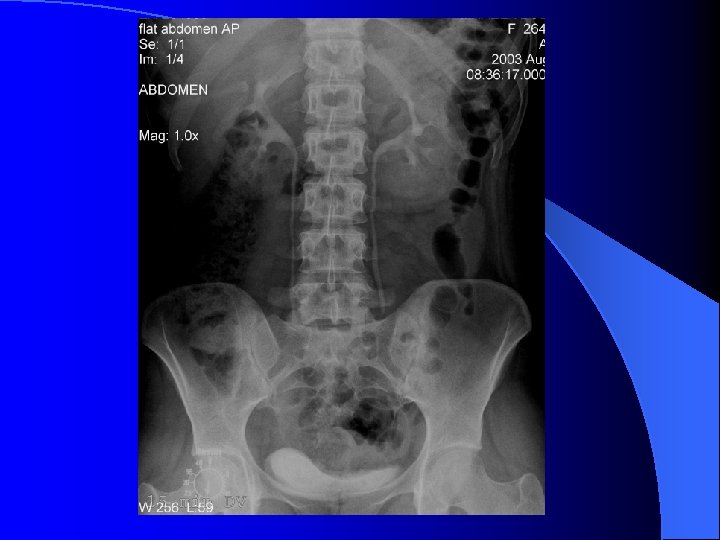

RRVS tehnic - ultimele doua coaste ( sup. ) - simfiza pubiana (inf. ) l calcificări - aparat urinar ( parenchim renal, calculi, prostatice ) - extraurinare ( arteriale, vezica biliara, pancreatice, ganglionare, fleboliti. . ) l umbre renale - pozitie, dimensiuni, contururi, intensitate l umbra m. psoas l

RRVS Nefrograma normală